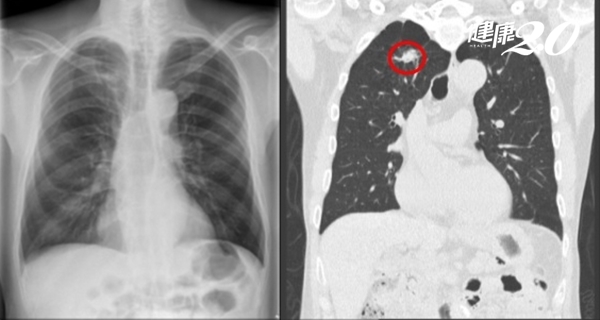

▲ 患者X光影像未顯示肺癌(左圖);肺部電腦斷層影像中,肺癌清晰可見(右圖)。

很多人以為「定期胸部X光檢查就能發現早期肺癌」,澄清醫院柏忕健康管理中心醫學影像科醫師洪盈盈澄清,這是錯誤的觀念;事實上,1公分以下的肺部腫瘤很難發現,甚至是1.5公分的腫瘤也不一定能看得到。

洪盈盈說明,因為很多肺癌早期生長時密度很低,呈現出來的毛玻璃影像看起來淡淡的,也有可能藏在胸椎、心臟、肋骨、橫膈膜或肝臟前後方,這些都是X光檢查的死角。